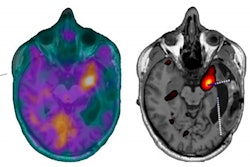

Nodal immune flare: 72-year-old patient with NSCLC received a neoadjuvant treatment with three cycles of ICIT + C (carboplatin/pemetrexed/pembrolizumab). 12 weeks after treatment began, the patient showed an increase in size and FDG avidity but also major pathologic response with less than 10% of vital tumor burden (ypT1a, No, Ro [local]). All figures courtesy of Dr. Daria Kifjak and Dr. Lucian Beer.